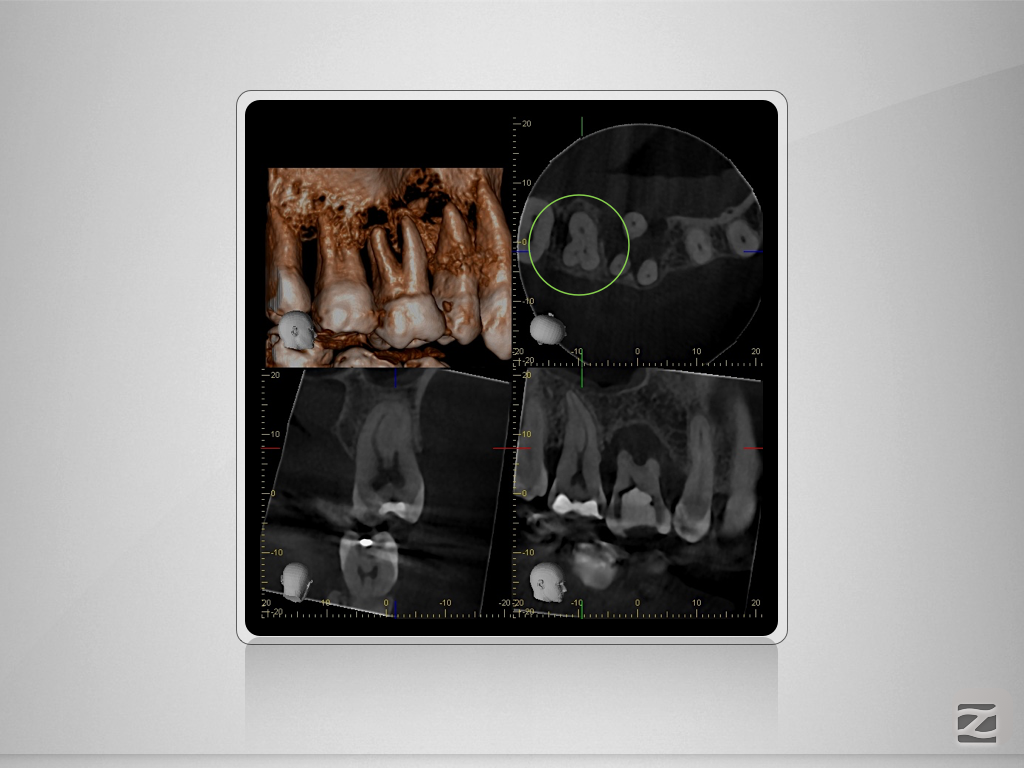

17D.007

Gewusst, wo’s lang geht.